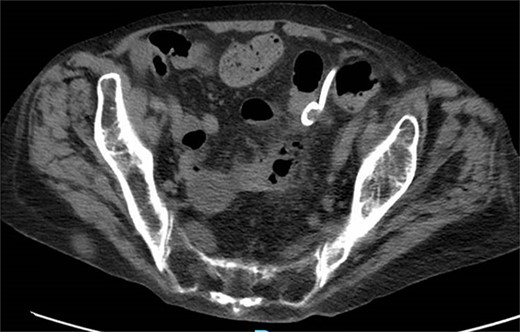

A 65-year-old female with a history of hyperlipidemia, hypertension, hip replacement, lumbar spinal fusion, chronic pain management, and prior laparotomy for endometriosis presented with a 3-day history of nausea, vomiting, and abdominal pain. She had no prior history of diverticulosis or colonoscopy. On examination, she was afebrile and hemodynamically stable. Physical examination revealed left lower quadrant tenderness, swelling, erythema, and fluctuance, suggesting an abdominal wall abscess (Figs 1 and 2). Laboratory tests showed leukocytosis with a count of 24.6 and a positive urinalysis with 2+ leukocytes. A CT scan of the abdomen and pelvis revealed a 3.8 × 3.6 cm air and fluid pocket in the low left anterior abdominal wall, indicative of an abscess likely at the site of a previous drain (Fig. 3). Additionally, there was a 2.8 × 1.8 cm irregular air pocket in the left pelvis, where an abscess had been identified in prior imaging.

CT from readmission with anterior abdominal wall abscess and left pelvic abscess.

One month prior, the patient was admitted for complicated perforated sigmoid diverticulitis. Treatment included piperacillin-tazobactam (Zosyn), bowel rest, and fluid resuscitation. On hospital Day 6, her condition worsened with increased nausea, vomiting, and an elevated WBC count of 15. CT imaging revealed a 4.8 × 4.4 × 4.0 cm diverticular abscess, leading to CT-guided percutaneous drainage by interventional radiology (Figs 4–7). Cultures grew Citrobacter sedlakii and Enterococcus faecium vancomycin resistant Enteroccus (VRE), and treatment was adjusted to include Bactrim, followed by daptomycin and levofloxacin. The abscess resolved after 3 weeks, and the drain was removed before discharge. The patient was instructed to follow up with her surgeon and undergo a 6-week interval colonoscopy.

CT showing resolution of abscess with IR pigtail drain in place.